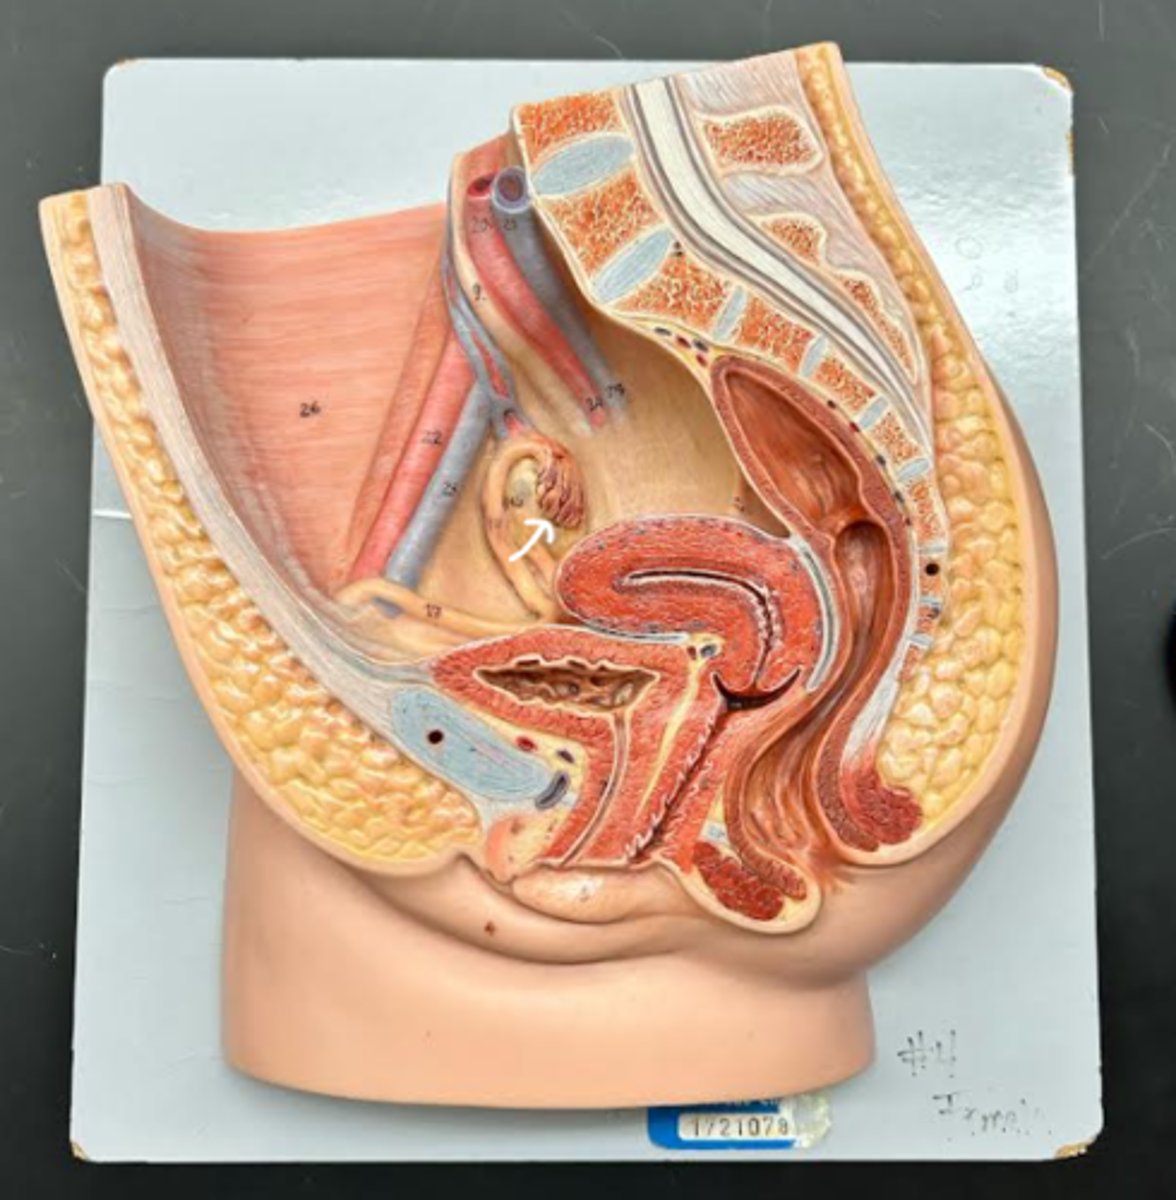

Chapter 29 Anat Phys: Female Reproductive System

Vagina

Vaginal orifice

Hymen

Vaginal fornix

Ovary

Fallopian tube

Fimbriae

Infundibulum

Ampulla

Isthmus

Uterus

Perimetrium

Myometrium

Endometrium

Fundus

Body of uterus

Cervix

Internal os

Cervical canal

External os

Labia majora

Labia minora

Prepuce

Vestibule

Clitoris

External urethral orifice